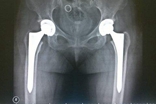

擅長(zhǎng):類風(fēng)濕關(guān)節(jié)炎、骨關(guān)節(jié)炎、強(qiáng)直性脊柱炎、股骨頭壞死、髖發(fā)育不良、血友病性關(guān)節(jié)炎、痛風(fēng)性關(guān)節(jié)炎等各種髖、膝復(fù)雜病例的人工關(guān)節(jié)置換。在感染、無(wú)菌性松動(dòng)、假體周圍骨折等原因?qū)е碌娜斯りP(guān)節(jié)翻修手術(shù)方面經(jīng)驗(yàn)豐富,治療水平國(guó)內(nèi)領(lǐng)先。

置換人工關(guān)節(jié)后千萬(wàn)別忽視小傷口置換人工關(guān)節(jié)后,病人應(yīng)該重視發(fā)燒、拔牙等可能造成血源性感染以及骨折等情況。[詳細(xì)]

國(guó)內(nèi)換關(guān)節(jié)為啥總“卡”在65歲?何時(shí)手術(shù)要看病人自己的感受,因?yàn)槊總(gè)人對(duì)生活質(zhì)量的要求不同。但隨著人工關(guān)節(jié)的普及,以及生活狀況的改變,人工關(guān)節(jié)越來(lái)越被老年人所接受。[詳細(xì)]

置換人工關(guān)節(jié):解決疼痛 恢復(fù)功能是否要做手術(shù),首先看年齡。其次要衡量實(shí)際疼痛,以行走能力來(lái)判斷,如果走不了500米,說(shuō)明疼得比較重。最后,能不能伸直是判斷關(guān)節(jié)變形嚴(yán)重程度的指標(biāo)。[詳細(xì)]